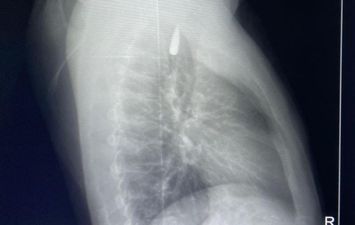

وقال الدكتور تامر عبد الله، عميد كلية الطب ورئيس مجلس إدارة المستشفيات الجامعية، أن المقذوف كان قد استقر على إثرها داخل تجويف القفص الصدري قرب الشريان الأورطي، وهو أكبر وأهم شرايين الجسم والمسؤول عن تغذية جميع الأعضاء الحيوية.

وأضاف أن الفريق الطبي، رغم دقة الحالة وتعقيدها، نجح في استخراج المقذوف بأمان بعد عملية جراحية نادرة استمرت عدة ساعات داخل المستشفى الجامعي الجديد، حيث خضع المريض بعدها للرعاية الطبية اللازمة، وحالته حاليًا مستقرة وتحت المتابعة الدقيقة من الفريق المختص.